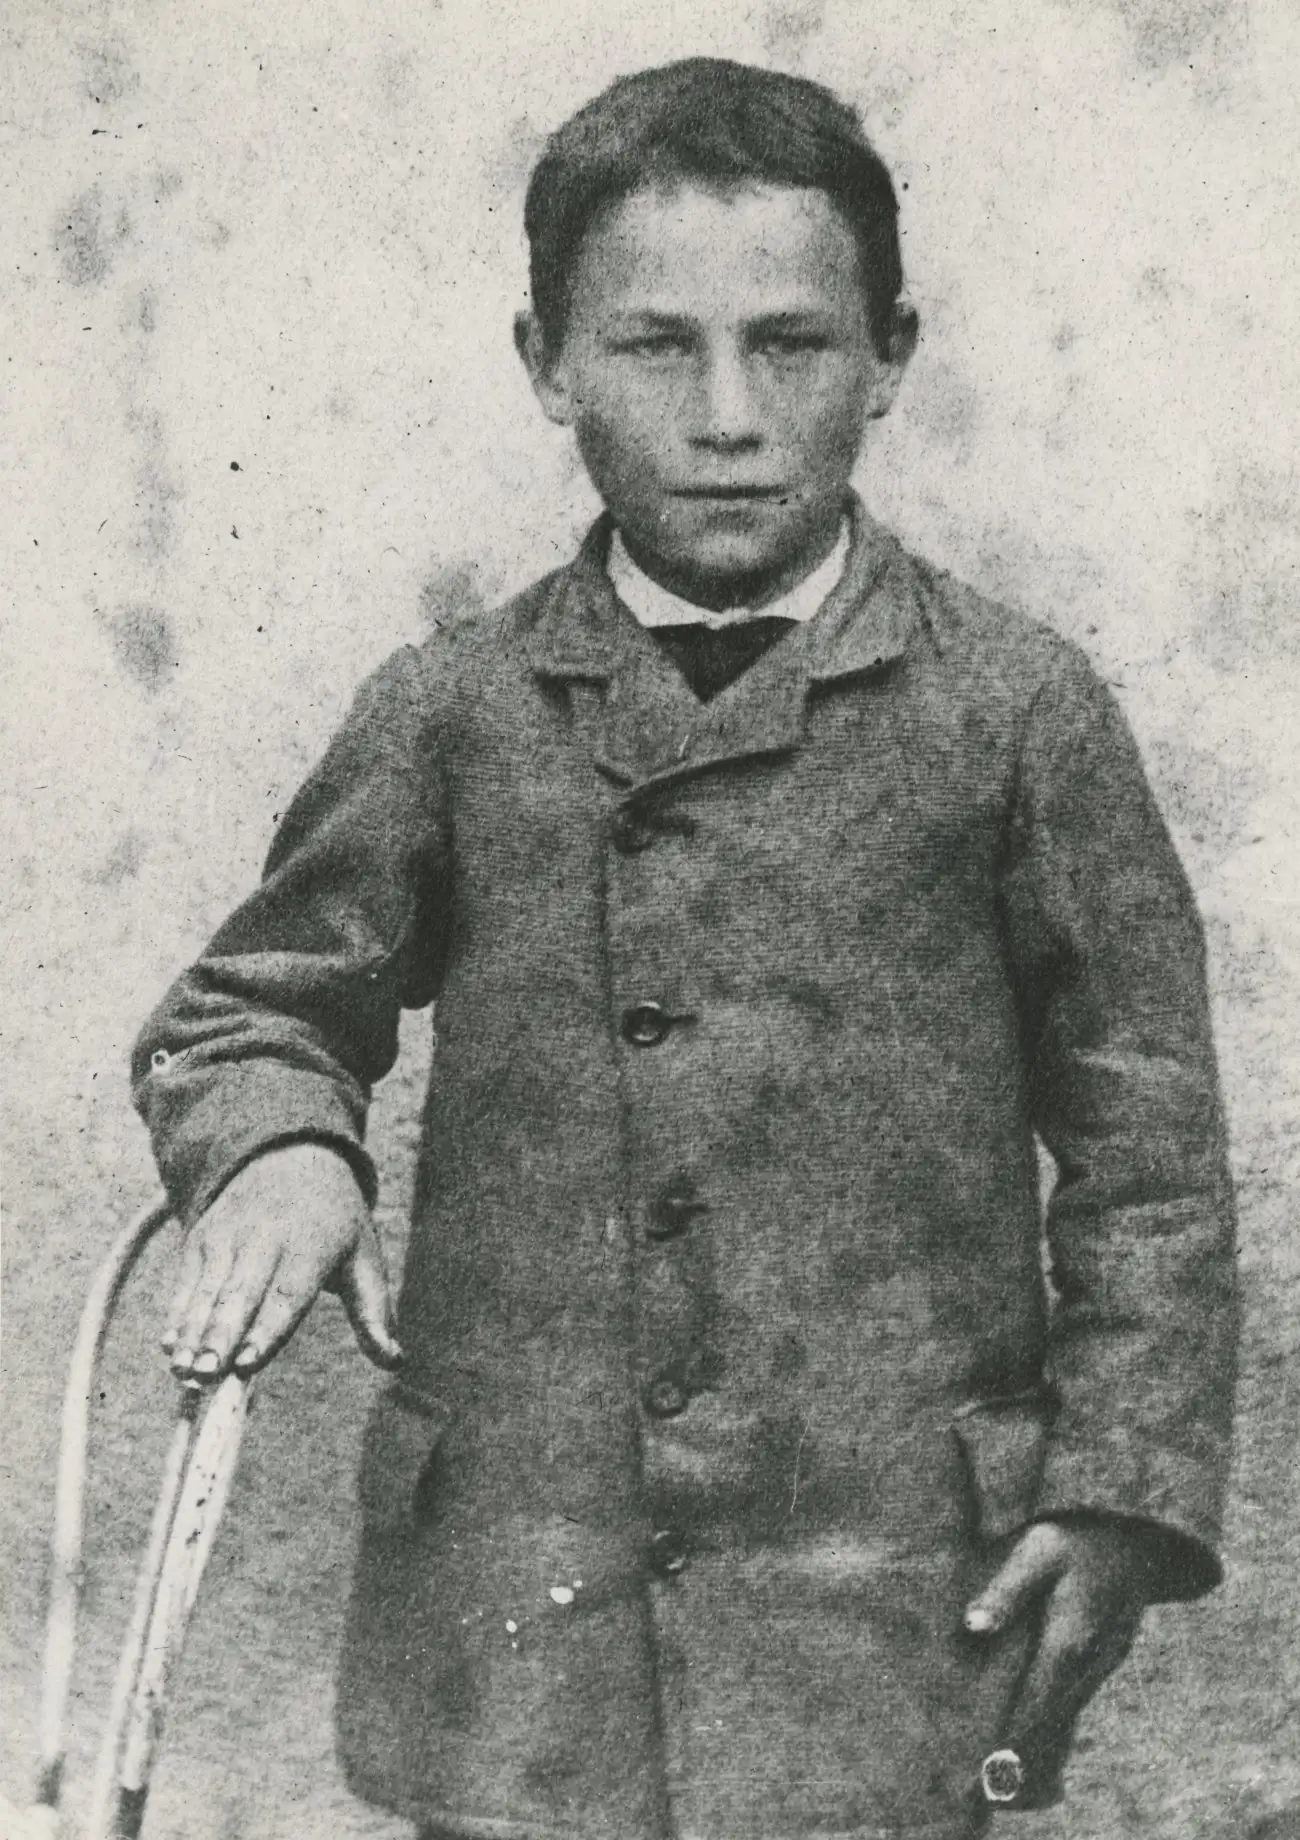

1885年7月6日的巴黎,一个九岁的男孩站在路易·巴斯德的实验室里。约瑟夫·迈斯特来自阿尔萨斯地区,两天前被一只疯狗咬了十四次。他的母亲听说巴黎有一位科学家正在研究狂犬病疫苗,便带着儿子千里迢迢赶来求助。

约瑟夫·迈斯特在1885年的照片,当时他被路易·巴斯德的狂犬病疫苗拯救,成为历史上第一个接受狂犬病疫苗的人类。

约瑟夫·迈斯特后来成为了巴斯德研究所的看门人,在那里工作了数十年。1940年,德国纳粹占领巴黎。据说迈斯特选择自杀而不是让纳粹进入巴斯德的陵墓。这个故事的真实性有争议,但它已成为狂犬病疫苗史上一个动人的注脚。